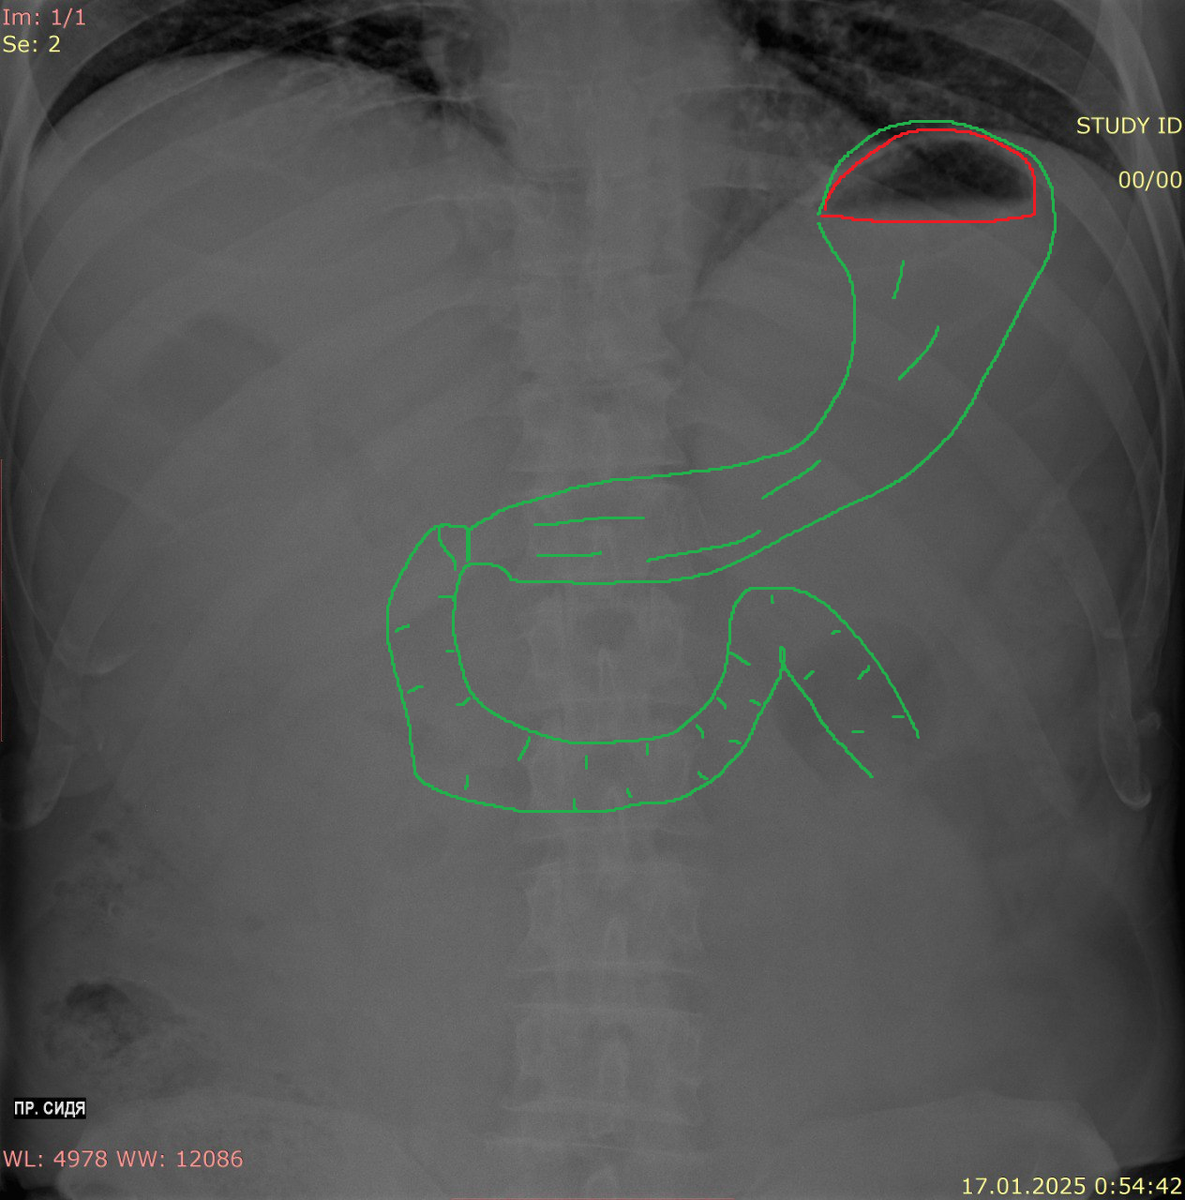

Желудок располагается в верхней части живота слева, имеет характерные контуры, которые видны на рентгене.

Тонкая кишка, состоящая из двенадцатиперстной кишки, тощей и подвздошной кишки, сопровождается характерными изгибами и петлями. Толстый кишечник, в свою очередь, образует «перевернутую U»-образную конфигурацию, находясь по периферии брюшной полости.

В правой верхней части могут быть видны печень и желчный пузырь, тогда как в левом верхнем квадранте располагается селезенка. Почки находятся на уровне L1 (верхний полюс), и на рентгеновских снимках они выглядят как парные тени. Важным аспектом является то, что на рентгеновских снимках также может быть видно количество свободного воздуха или жидкости, что может выявить наличие патологий в брюшной полости.